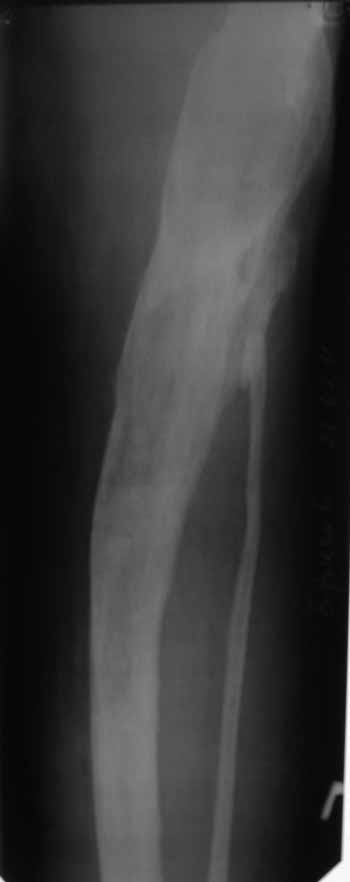

Пациент 29 лет. Неоднократно оперированная Coxa Vara.

В анамнезе этапные операции по поводу устранения Coxa Vara, формирование артродеза коленного сустава, удлинения бедра. В данный момент беспокоит укорочение 7 см, эквинус стопы. Объективно: - местный статус виден на фото, сосудистых и неврологических расстройств нет. Обратился в консультативном порядке, настроен на удлинение голени в г.Волгограде. (со слов больного - не берут без санации очага на голени). Ваши предложения? Из кулуарных соображений - а не актиномикоз ли это? Иссечение рубцов+ VAC+ Стержень с аппаратом + микрососудистый трансплантат(?)

Ваш вопрос, коллега, вполне правомерен. В советское время те из нас, кто занимался костно-гнойной инфекцией видели достаточное количество подобных несчастных, кочующих из стационара в стационар. Своеобразный госпитализм приводил к тому, что люди тратили всю свою, как правило достаточно короткую жизнь, на лечение зачастую реально неизлечимых процессов. В данном случае имеющаяся рентгенологическая картина груботрабекулярной перестройки кости, сочетающаяся с участками склероза говорит, скорее всего, о том, что вся имеющаяся картина, дополненная чудесными фотографиями,вполне укладывается в клинику гематогенного остеомиелита, которым и страдает пациент с детства. Никакие санации, к сожалению, не приведут в данном случае к излечению, так как все имеющиеся рубцы являются зоной жизни этой самой инфекции. При продолжении лечения не исключено достаточно раннее развитие амилоидоза в этом случае. Мне кажется, что оптимальным было бы определить пациента в институт протезирования и протезостроения или в то учреждение, которое в регионе выполняет данную функцию. Специалисты помогли бы определиться с уровнем ампутации, являющейся, по сути, единственным способом разорвть порочный круг и дать пациенту возможность какой-то социальной адаптации. А в плановом порядке, насколько мне известно, можно добиться неплохого финансового обеспечения под протез конечности по квоте. Другого решения здесь нет. С уважением, Андрей Волна

извините за очепятку - не берут без санации очага на бедре. Сейчас имеется отделяемое из нижнего свища с периодическим выходом секвестром в виде мелкой крошки. Движений в ТБС почти нет - есть только сгибание градусов до 10. В стопе - только качательные.